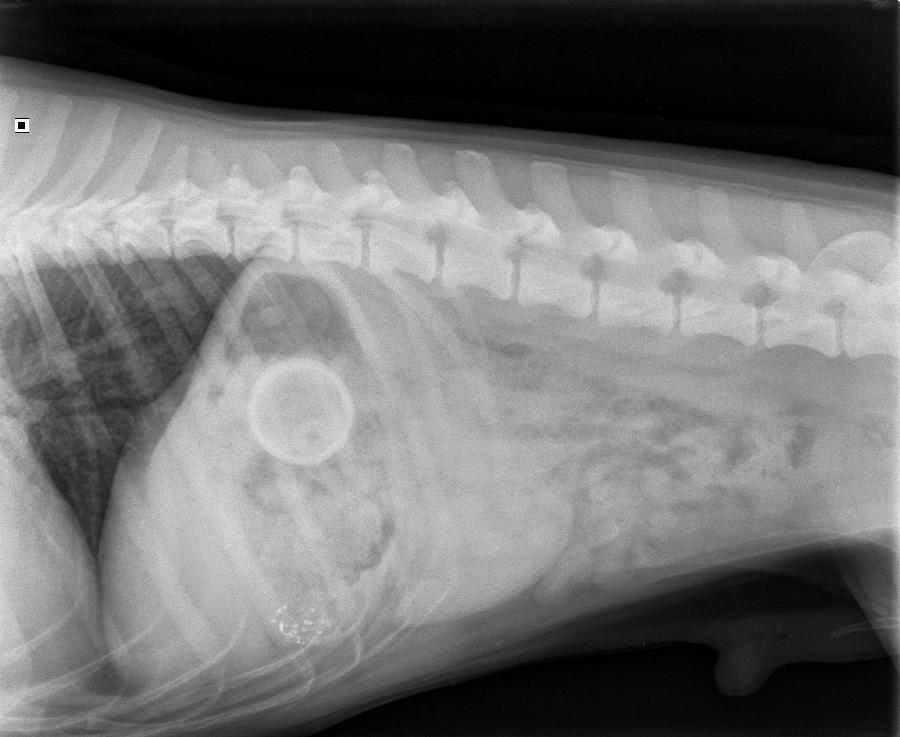

Op 5 maart 2020 werd de kruising Appenseller x labrador Brasso aangeboden op de praktijk. Brasso braakte en de eigenaar miste een klein tennisballetje.

Op de foto was goed te zien waarom brasso braakte, én waar het balletje was. We hebben Brasso geopereerd en het balletje uit de maag gehaald. Brasso werd vlot wakker en is heel goed hersteld van de ingreep. Of Brasso hiervan geleerd heeft? Dan weten we (nog) niet...

Op de röntgenfoto is het balletje goed te zien